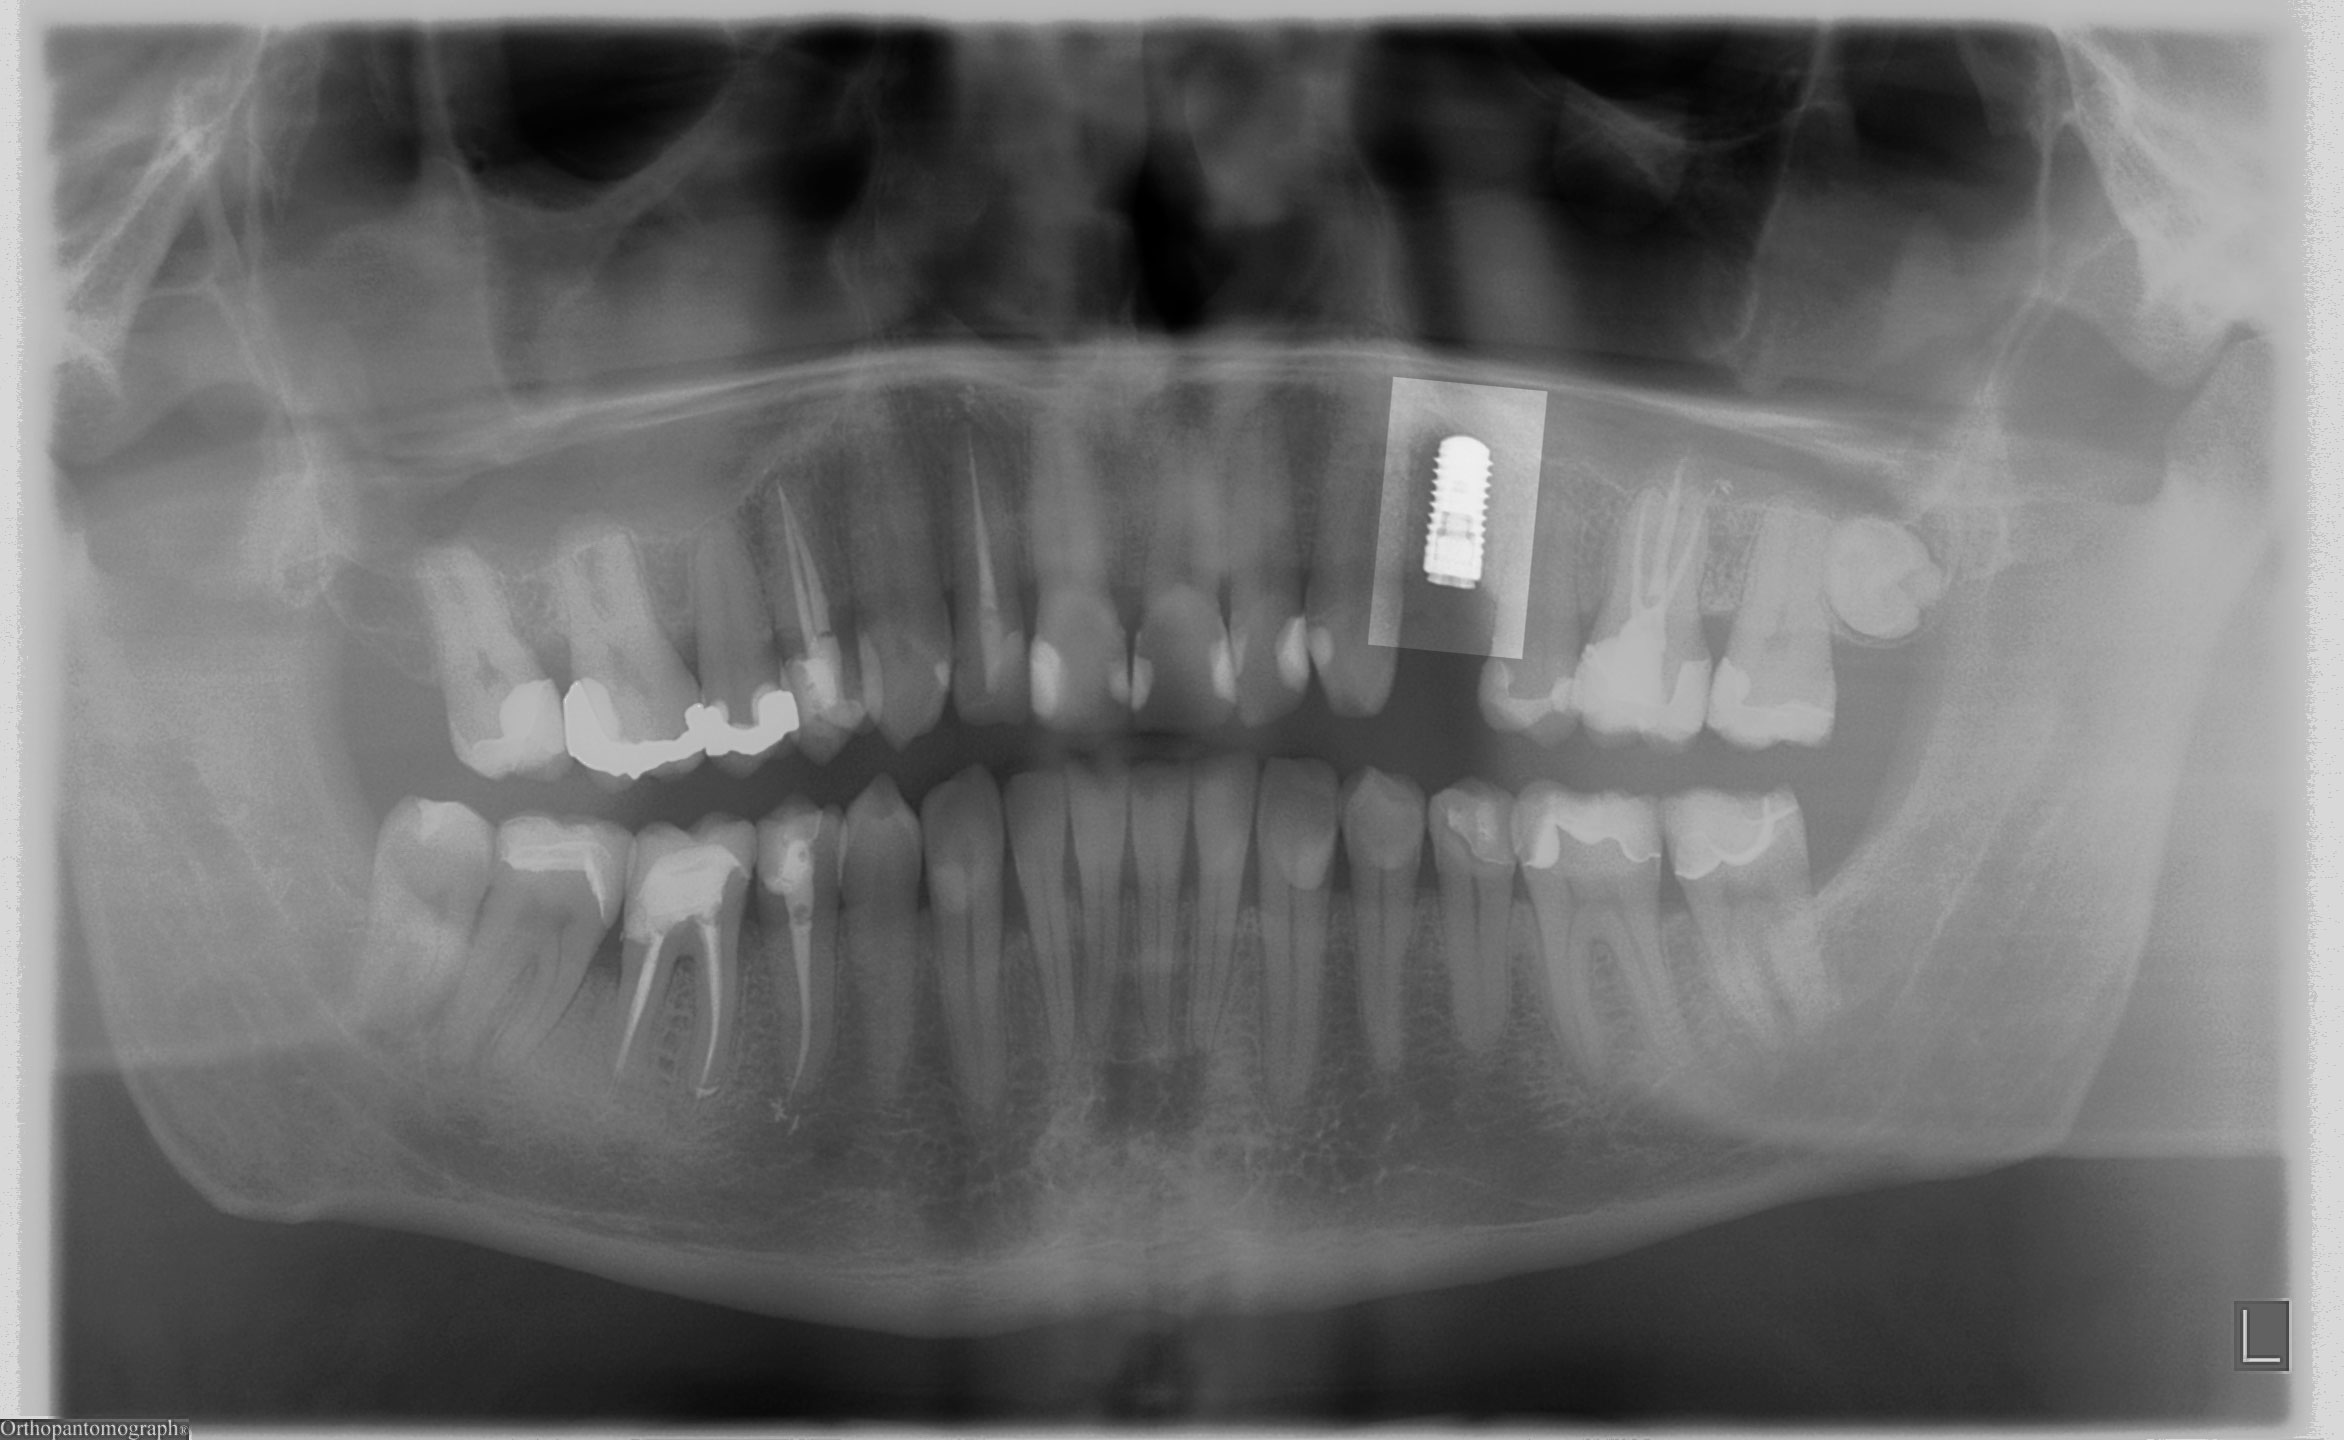

Wir haben die Implantate (Straumann BL) im Oberkiefer eingesetzt. Gleichzeitig wurde der letzte Zahn oben rechts (im Bild links) parodontal-chirurgisch behandelt: Entfernung des Biofilms, der Konkremente und Knochenaugmentation im vertikalen zweiwandigen Defekt. Das Implantat unten links wurde vor mehreren Jahren von uns inseriert und prothetisch versorgt.